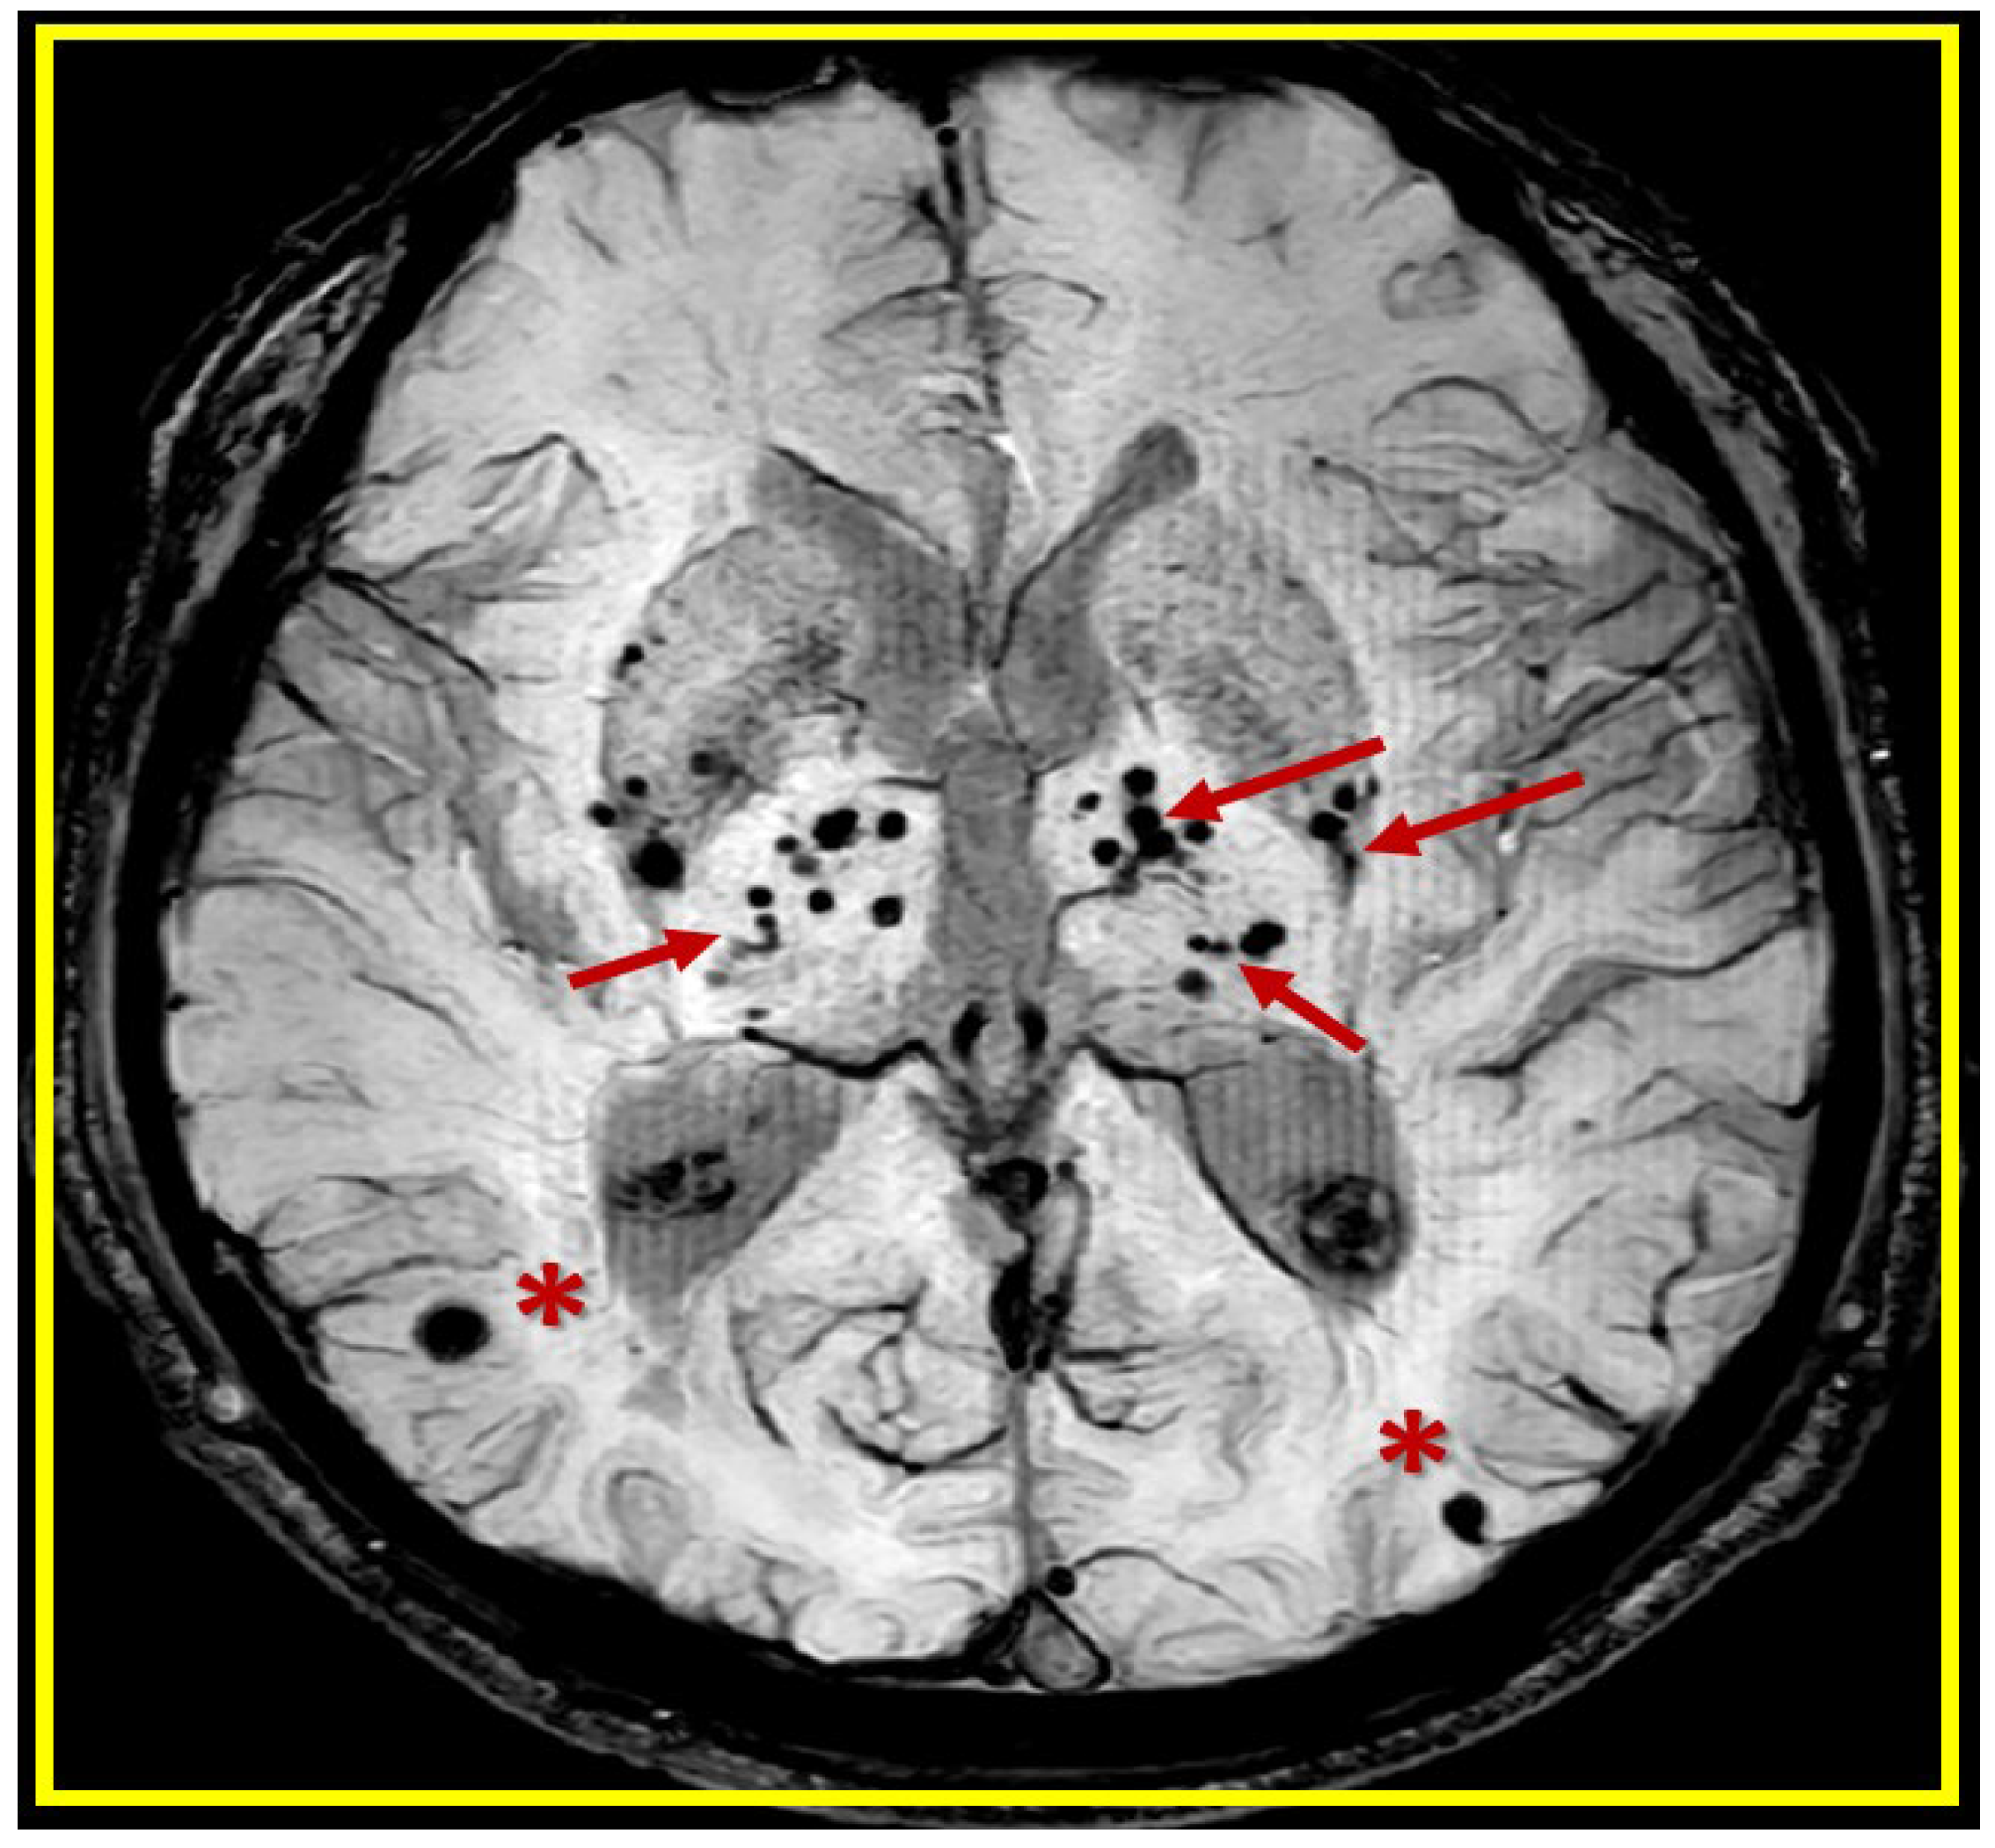

Figure 1.

Cerebral microbleeds (CMBs) pathologic lesions with varying sizes (usually 2-5 mm and less than 10mm) and different locations (lobar (red asterisks) verses deep, infratentorial, white matter basal ganglia (BG) (red arrows) in T*2-weighted gradient recall echo (GRE)/susceptibility weighted images (SWI) MRI images. This revised image provided with permission by CC 4.0 [

4].